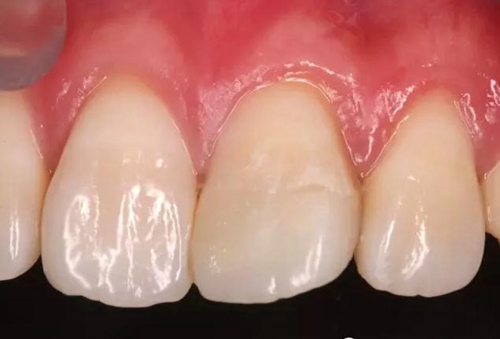

術(shù)后即刻口內(nèi)照

口內(nèi)檢查:21切端牙體色澤恢復(fù),唇側(cè)面見(jiàn)水平向粘接界面,殘留少許樹(shù)脂水門(mén)汀,牙齦腫脹較前消退,叩-,松-。

處理:21唇側(cè)沿粘接界面磨除少量牙釉質(zhì),